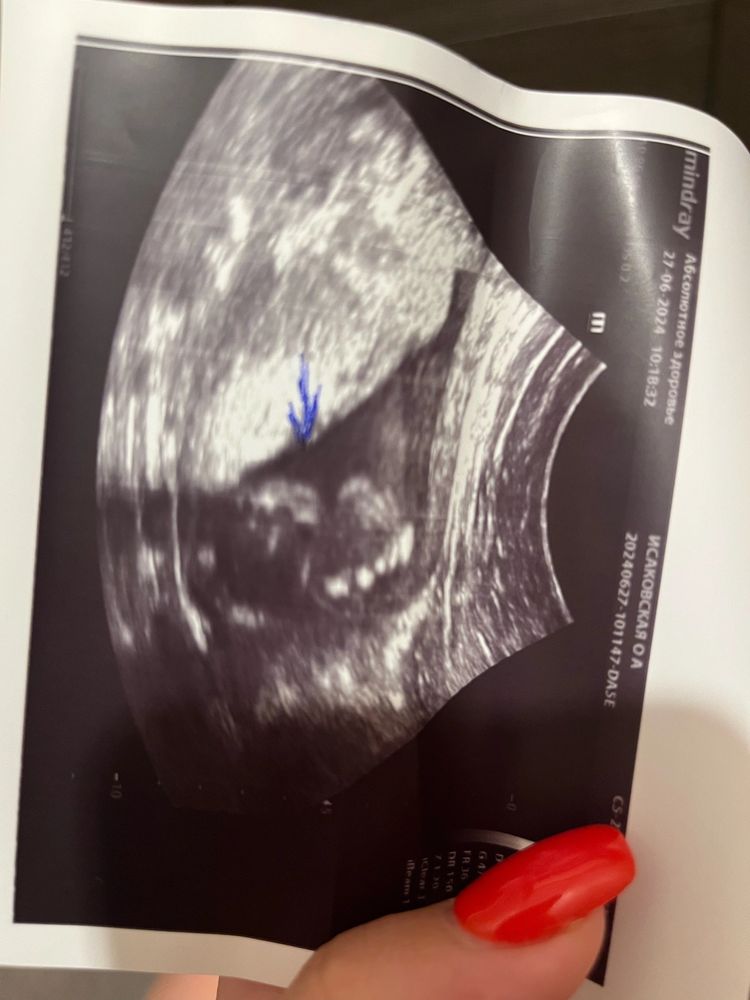

Пол малышаВсем привет) была в 17 недель на опредение пола ,сказали 100% девочка (снимок 1)

1 снимок девочка